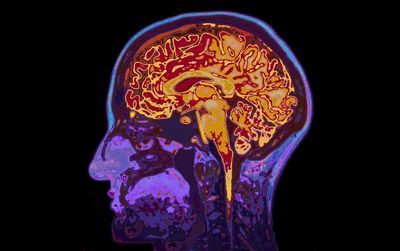

They reached this conclusion by studying the functional magnetic resonance imaging (fMRI) data of over 19,000 people. This type of MRI visualizes brain activity, helping researchers to pinpoint which parts of the brain appear to be in decline and, when taken multiple times, when they are declining.